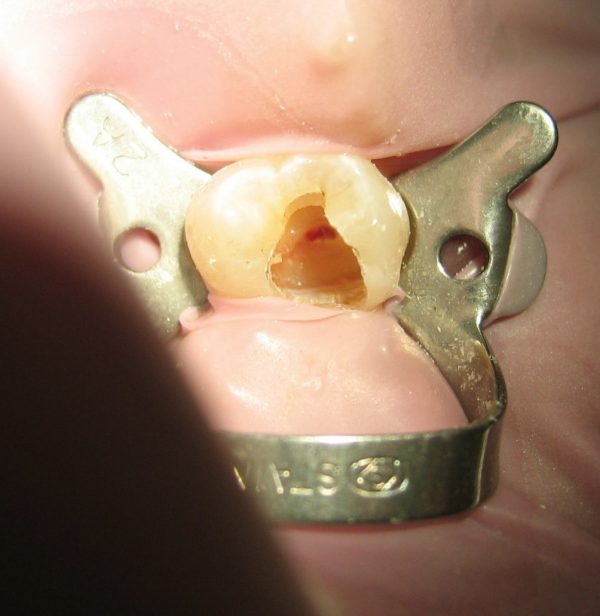

ابتدا یک حفره داخل دندان ایجاد می شود. پالپ، همراه با باکتری ها و ذرات مربوط، از داخل دندان تخلیه می شوند. روند پاکسازی با استفاده از فایل های درمان ریشه تکمیل می شود. یک دسته از این فایل ها که قطر آنها به ترتیب افزوده می شود، به نوبت داخل حفره دسترسی قرار داده می شوند و تا انتها داخل ریشه دندان کار می کنند تا اطراف داخل ریشه دندان را بتراشند. از آب یا هیپوکلریت سدیم به صورت دوره ای برای شستن ذرات استفاده می شود.

وقتی دندان به طور کامل پاکسازی شد، لازم است سیل شود. برخی دندانپزشکان ترجیح می دهند قبل از سیل کردن دندان یک هفته صبر کنند. برای مثال، اگر عفونتی وجود داشته باشد، ممکن است دندانپزشک مقداری دارو داخل دندان قرار دهد تا آن را ریشه کن نماید. برخی دیگر نیز ترجیح می دهند دندان را همان روزی که پاکسازی می کنند سیل کنند. اگر درمان ریشه در یک روز تکمیل نشود، یک پر شدگی موقت داخل حفره دندان قرار داده میشود تا بین دو جلسه درمان آلودگی ها را از آن دور نگهدارد.